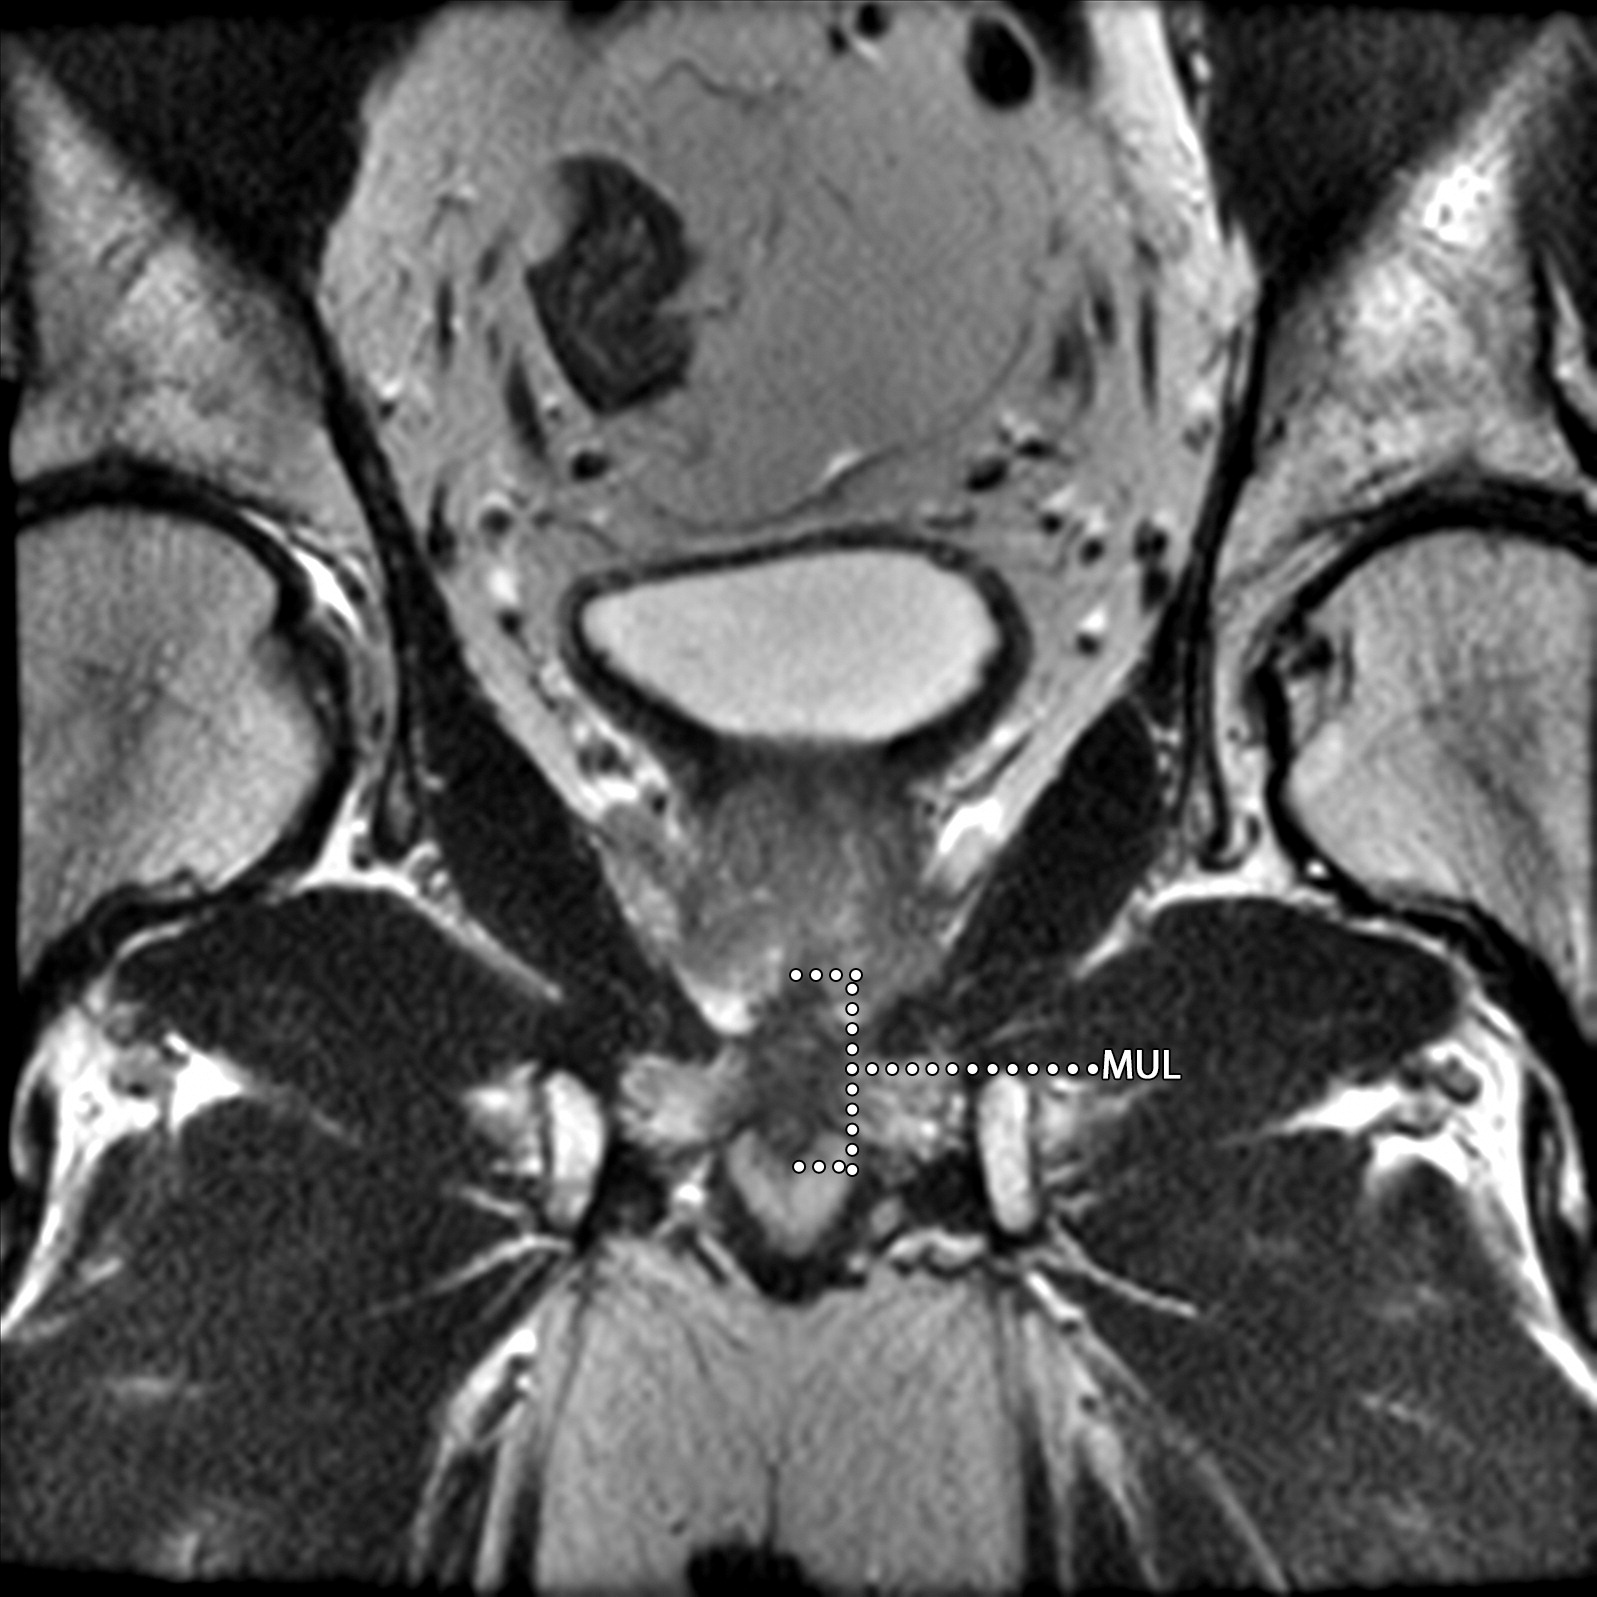

膜性尿道长度(MUL)的测量,注意膜性尿道的近端被前列腺尖端覆盖。